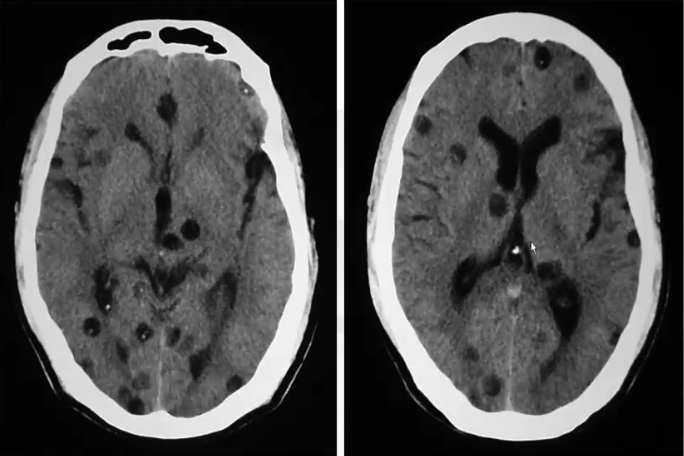

❖ 脑实质型的囊虫病病理上分为4期,各期的CT表现:

I期为囊泡期:平扫表现为脑实质内单发或多发的小圆形囊性低密度影。典型者囊泡内可见小结节状等密度影,即囊尾蚴的头节。增强扫描多数低密度灶不强化,少数呈结节状或环状强化。

Ⅱ期为胶样囊泡期:病灶密度增高,头节逐渐消失,周围水肿明显,增强扫描可见环形强化。

Ⅲ期为结节肉芽肿期:平扫呈不规则低或稍高密度灶,周围可见不同程度水肿,增强后呈结节样或环形强化。

IV期为钙化期:高密度影,增强后病灶不强化。